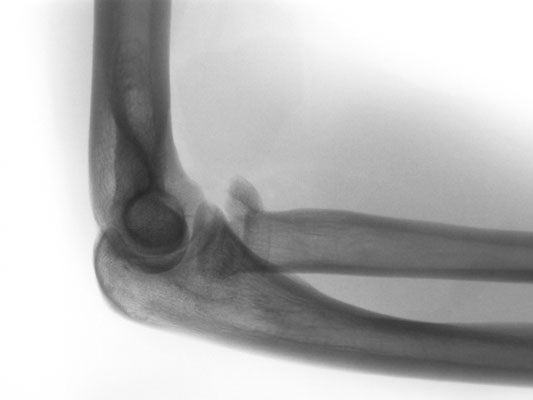

Das Ellbogengelenk ist ein komplexes Gelenk, an dem 3 Knochen beteiligt sind (Oberarm, Elle, Speiche). Hauptbewegungsebenen sind die Streckung und Beugung, sowie die Umwendung des Unterarmes. Prinzipiell kann jeder der 3 Knochen alleine für sich gebrochen sein, häufig sind auch Kombinationen von mehreren Brüchen.  Eine Verrenkung des Ellenbogengelenkes (Luxation) führt immer zu einer Verletzung des Bandapparates und/oder knöchernen Schäden.

Luxationen mit oder ohne zusätzliche Knochenbrüche

In Kombination mit dem auf dem Röntgenbild sichtbaren Knochenbruch liegen häufig zusätzliche Bandverletzungen des Gelenkes vor.